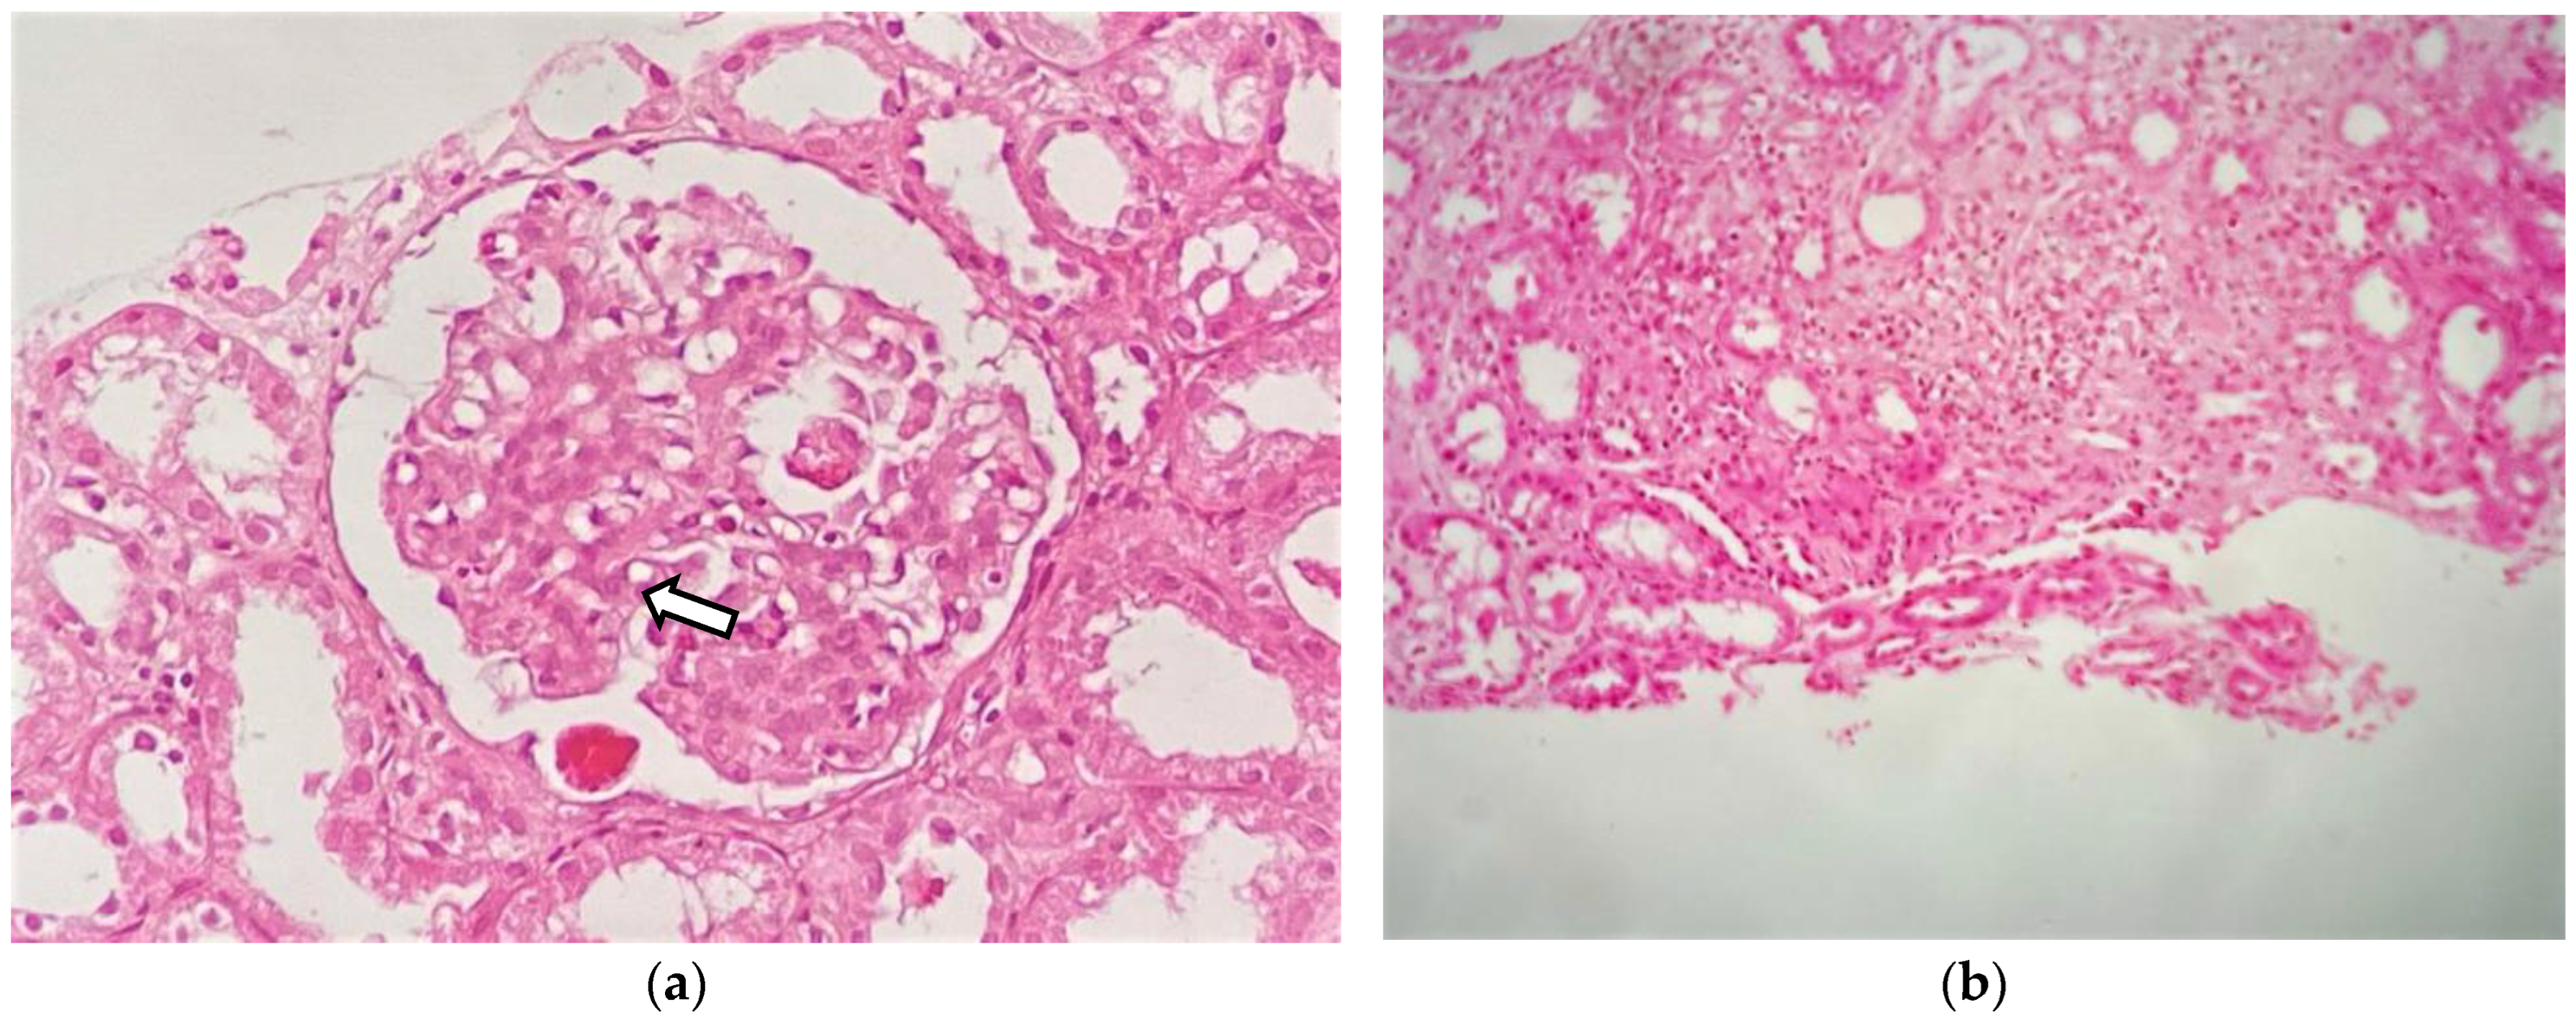

Given the renal involvement, characterized by a nephrotic/nephritic syndrome, a renal biopsy (RB) was performed. Light microscopy (LM) showed 18 glomeruli, 1 of which (5.5%) was globally sclerotic. The rest showed lobular accentuation, expansion, and proliferation of mesangial cells (2+), the occasional presence of polynuclear cells in capillaries, 2–5 eosinophils, and in addition, thickening and segmental unfolding of capillary loops, and 3 of 18 glomeruli showed cellular crescents and red blood cells in capillary lumens (1+). Tubules showed turbid degeneration and hematic casts. The interstitium showed a lymphoid infiltrate and mild eosinophils. Arteries and arterioles were unremarkable (Figure 2a,b). Congo red and thioflavin staining were negative. The frozen tissue immunofluorescence (IF-F) study was negative for IgG, IgA, IgM, C3, C4, LCκ, LCλ and fibrinogen. IF on pronase-digested paraffin-embedded (IF-P) sections was not performed in our case. The immunohistochemical staining study was negative for Anti-Phospholipase A2 Receptor Antibody (Anti-PLA2R), IgG4 and C4d. Electron microscopy (EM) revealed glomerular subepithelial granular 1+ glomerular deposits (humps) distributed in a disordered manner and of heterogeneous size, a basement membrane of capillary loops with sporadic thickened segments, endothelial cells with preserved fenestrations, no tubule reticular inclusions, and abundant cells in the lumen of the capillaries (eosinophils, neutrophils, and lymphomononuclear cells). Diffuse pedicellular effacement in podocytes and focal hyperplasia, increased mesangial matrix, tubular atrophy, and an interstitium with increased collagen and the presence of leukocytes and lymphomononuclear cells were observed. The vessels did not present significant alterations (Figure 3a,b). Based on the clinical course, and the analytical and histological findings of LM, IF, and EM, the diagnosis was diffuse membranoproliferative glomerulonephritis (MPGN) due to deposition of unorganized immune complexes, secondary IHES. In view of the above results, and in the presence of a massive nephrotic proteinuria with AKI, it was decided to start treatment with glucocorticoids (GC), at a dose of 1 mg/kg/day of prednisone (PDN) with progressive tapering after 2 weeks and discontinuation at 12 weeks and hydroxyurea, which was administered initially at 2 g/day for 7 days. The use of both drugs resulted in a favorable evolution characterized by a 50% reduction in eosinophilia concentration as well as a significant decrease in proteinuria and creatinine (Figure 4). After this improvement, the hydroxyurea dose was adjusted to 1.5 g/day for 10 days and subsequently 1 g/day for 14 days. However, an increase in the eosinophilia concentration was observed with this reduction, leading to increasing the dose to 2 g/day again. This adjustment achieved an adequate response for 14 days. Subsequently, the dose was reduced to 1 g and maintained for 90 days. However, in the third month after the start of treatment, the patient presented a new rebound in eosinophil values associated with the persistence of residual proteinuria of 1064 mg/g. In view of this situation, and in order to avoid the toxicity of hydroxyurea and GC minimization, it was decided to switch to imatinib at 400 mg/day. The patient responded very well to this new approach. At the 12-month follow-up, a reduction in the eosinophil concentration to below 800/L was noted, with creatinine levels of 0.74 mg/dL and 24 h urine protein of 334 mg (Figure 4). Response to treatment was favorable, evidencing a positive evolution in his clinical condition. The results coincided with a significant decrease in IgE concentration to values of 81.7 IU/mL (normal < 200 IU/mL). It was only necessary to add, as an antiproteinuric measure, a renin-angiotensin aldosterone system (RAAS) blockade; it was not necessary to add mineralocorticoid receptor antagonists (MRAs) or sodium-glucose transporter protein 2 inhibitors (SGLT2i), due to their decrease in proteinuria to non-nephrotic ranges. At the 16-month follow-up, he continued to have a normal eosinophil count, proteinuria, and renal function.

The LM of our patient showed mesangial expansion with mesangial cell proliferation and endocapillary hypercellularity with the presence of neutrophils and eosinophils in the capillary lumens. The presence of double contours and cellular crescents was also identified. In the interstitium, we observed a patchy inflammatory infiltrate composed of lymphocytes and eosinophils. The case reported by Ni H-F et al. [25] also described mesangial proliferation and eosinophilic infiltration in the tubulointerstitial, with IgM deposits. Curras-Martin´s case report [26] and Dong´s case series [6] reported the presence of eosinophil infiltration in the interstitium, and the latter 73% of patients had an infiltrate with the focal distribution. According to the studies reviewed, the presence of eosinophils in the glomerulus and cellular crescents is not common, as described by Dong´s case series [6].

Figure 2. Renal biopsy: (a) light microscopy shows a glomerulus with moderate mesangial hypercellularity (white arrow) (H-E staining; original magnification ×400); (b) interstitial inflammatory infiltrate composed of lymphocytes and eosinophils (H-E staining; original magnification ×200).